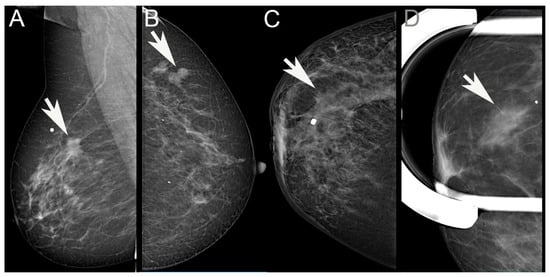

Two radiologists (ÉA, OS) involved in reporting screening mammography, retrospectively reviewed the mammographic images of the cases and independently categorized the cases as having either architectural distortion, an increase in density, circumscribed/lobulated mass, spiculated mass, or no radiological features (occult) (Figure 1); multiple categories could also be opted for the same mammogram. During the analysis, a hierarchical approach was also used: if a mass lesion was partly spiculated, partly lobulated, or circumscribed, it was considered spiculated; whenever there was a mass lesion, this was ranked first, and architectural distortion or increased density were considered only if there was no mass lesion in addition. Comments could be added, for example, if microcalcifications were present. The observers also recorded whether the lesion looked multifocal on mammography—MULT(MG). The period encompassed in the study involved digital mammography with a Giotto 3DL (until February 2021) or a Giotto Class (from February 2021) unit (both from IMS Giotto SpA, Sasso Marconi, Italy). From September 2021, tomosynthesis was also performed on 31 cases and reviewed within the frames of this study, making the morphological evaluation more delicate. The list selected on the basis of the pathology diagnoses included a few cases diagnosed elsewhere, and these had to be excluded from the radiology review. ILCs with discrepant individual categorization were then re-analyzed mutually to reach consensus on morphological features.

Figure 1. Examples of visible mammographic alterations evaluated in the study. (A): Spiculated mass; (B): Lobulated/circumscribed mass; (C): Architectural distortion; (D): Increased density. (Arrows point to the lesions. White dots label the cutaneous area where the patient palpated the lesions).